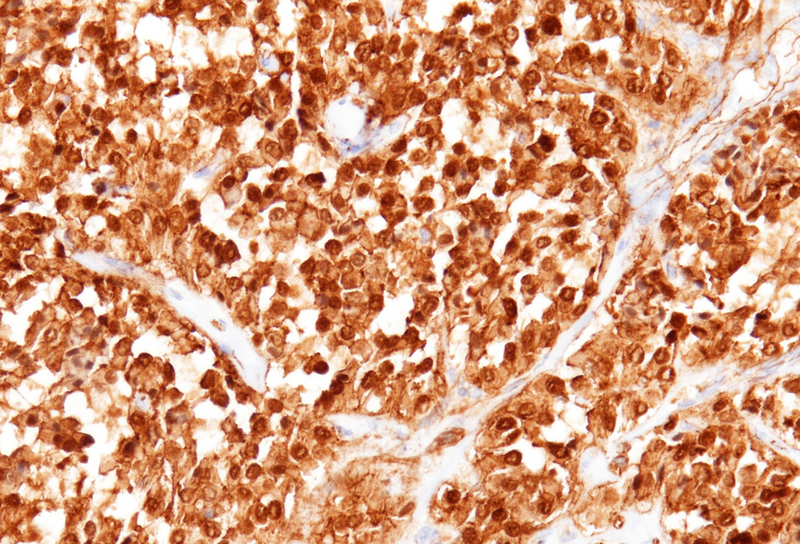

Immunohistochemically, the tumor cells showed diffuse and strong nuclear and cytoplasmic positivity for β-catenin (Panel E). They also expressed CD56/NCAM (Panel F), progesterone receptor (Panel G), CD10, and cyclin D1, with focal positivity for synaptophysin (Panel H). The tumor cells were negative for cytokeratins, chromogranin, and trypsin, and loss of membranous E-cadherin expression was observed. The Ki-67 proliferation index was low (<5%).